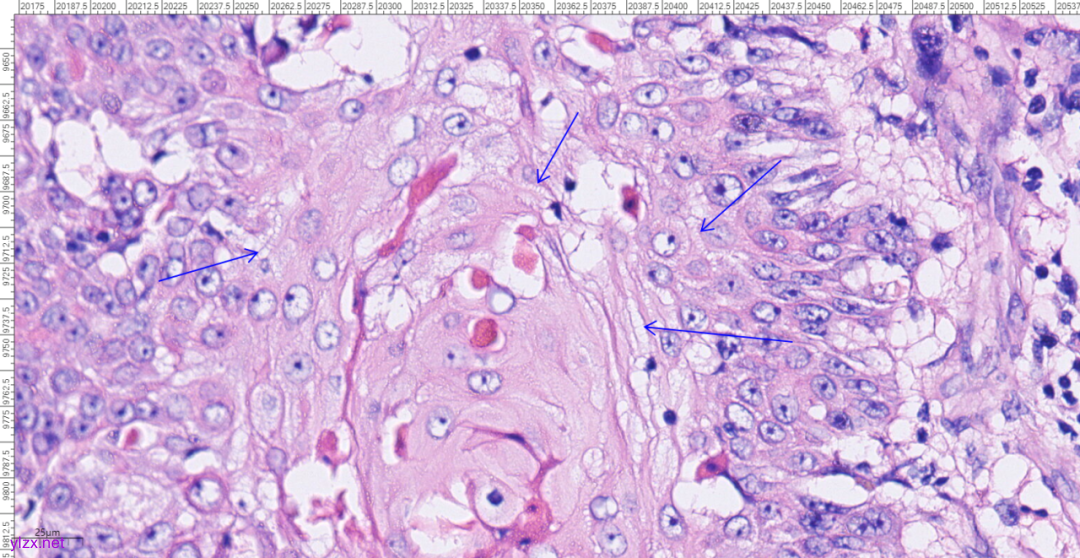

3.2镜下观(图3-图9):

低倍镜下可见卵巢肿物呈囊,中倍镜下,囊壁见分化成熟的多胚层成分,成熟型囊性畸胎瘤区域可见皮肤(正常鳞状上皮及其表明角化物)及其附属器成分(皮脂腺、汗腺及毛囊),局部囊壁表面可见由正常鳞状上皮-原位癌-鳞状细胞癌逐渐过渡;在鳞状细胞癌区域,囊壁增生的纤维结缔组织中可见肿瘤细胞呈巢状向下浸润性生长,也向囊腔内乳头状生长,局部癌巢中央可见角化珠及坏死;高倍镜下,鳞癌成分肿瘤细胞大小不等,细胞排列紊乱,细胞中-重度异型,核大深染,略呈空泡状,核仁明显,核分裂象易见,伴角化珠形成。

图6 在SCC区域,癌巢向下浸润性生长,也向囊腔内乳头状生长。

图7 高倍镜下,癌巢中央可见角化珠。

图8 高倍镜下,高分化鳞癌细胞之间可见细胞间桥。

图9 高倍镜下,中分化鳞癌细胞呈空泡状,核仁明显,核分裂象易见。

镜下观:

MCT-SCC在形态学上分为MCT和鳞状细胞癌两种成分,其中MCT镜下可见由发育成分化良好的外胚层、内胚层和中胚层组织,如牙齿、头发、骨骼和皮脂腺。SCC镜下见增厚的囊壁处有鳞状细胞癌成分,表现为异型增生的鳞状上皮细胞突破基膜向间质延伸,增生的纤维结缔组织中见肿瘤细胞排列成巢状,细胞大小不等,排列紊乱,核分裂象易见;可见同心圆排列的角化珠。病理医师应对标本充分取材进一步提高其诊断水平。